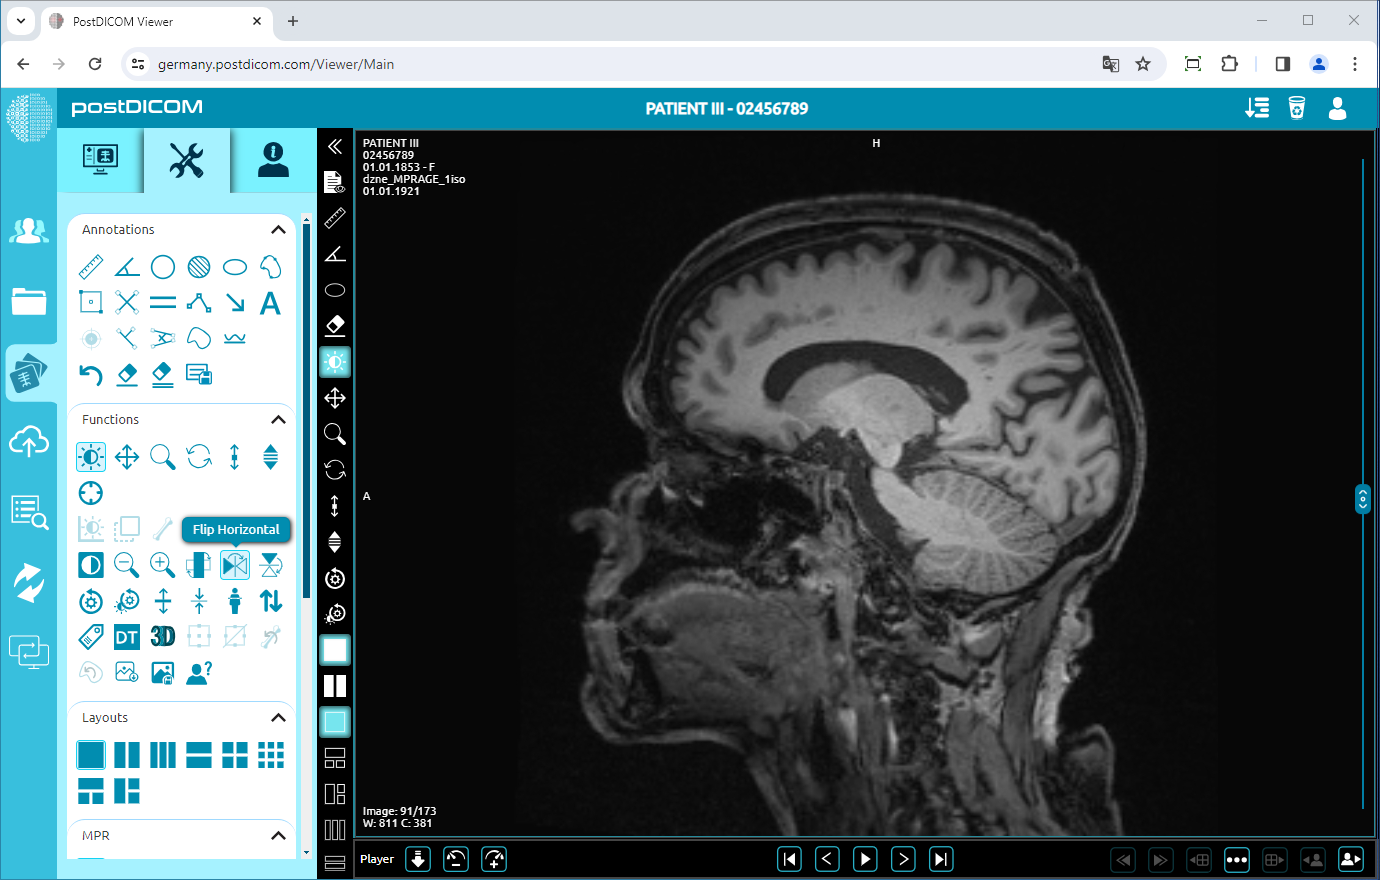

Flip Horizontal

To flip the image horizontally, click on the “Flip Horizontal” icon on the left side of the page.

After clicking, the horizontal mirror view of your image will be displayed on the viewport.